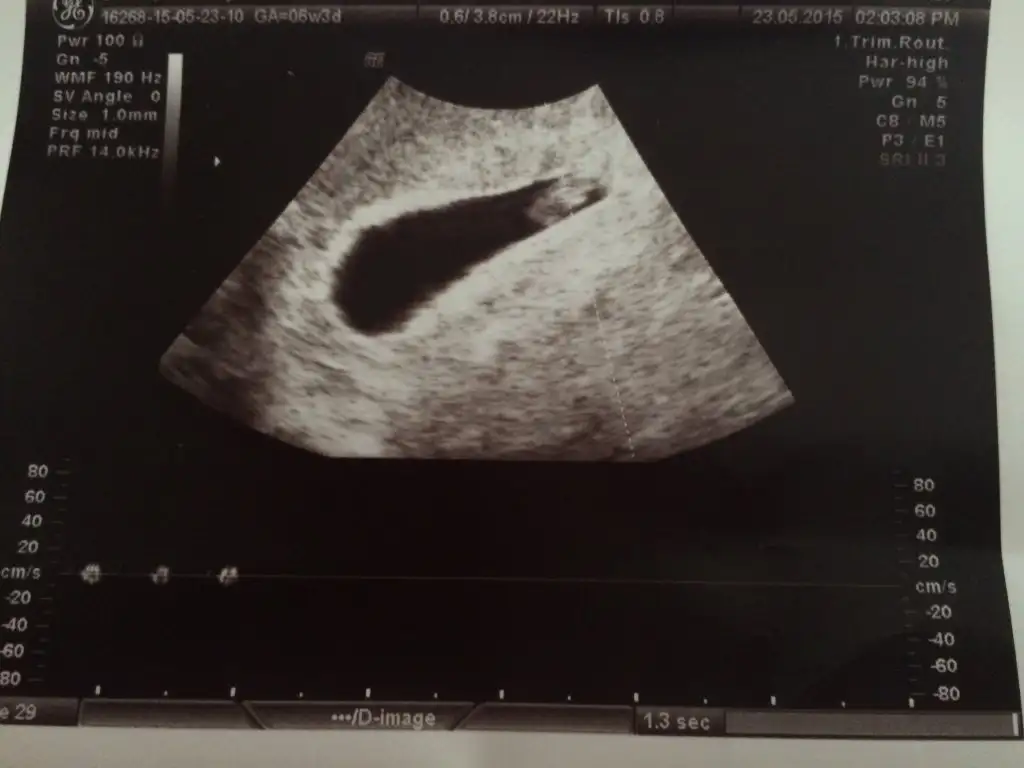

Merhaba arkadaslar bana da yorum yapabilirmisiniz 7 hafta 3 gunluk burda bi kizim var bu bebegimin cinsiyetini cok merak ediyorum

Eklentiler

• IMG-20150522-WA0000.webp

IMG-20150522-WA0000.webp

33,6 KB · Görüntüleme: 189